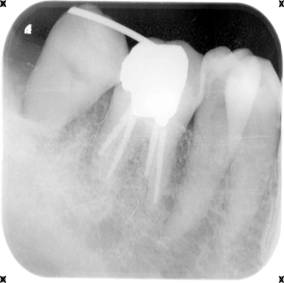

以下の写真は親知らずを手前の第二大臼歯に移植した症例のレントゲンです。

| 第二大臼歯は虫歯がひどく崩壊しています。保存不可能なため、抜歯して、後ろから親知らずを移植します。 | 親知らずを抜歯して、第二大臼歯に移植しました。手前の第一大臼歯とワイヤーで固定しています。 | 根の治療をしてかぶせものをして治しました。 |

| 親知らずを抜歯して、第二大臼歯に移植しました。手前の第一大臼歯とワイヤーで固定しています。 |

| 根の治療をしてかぶせものをして治しました。 |